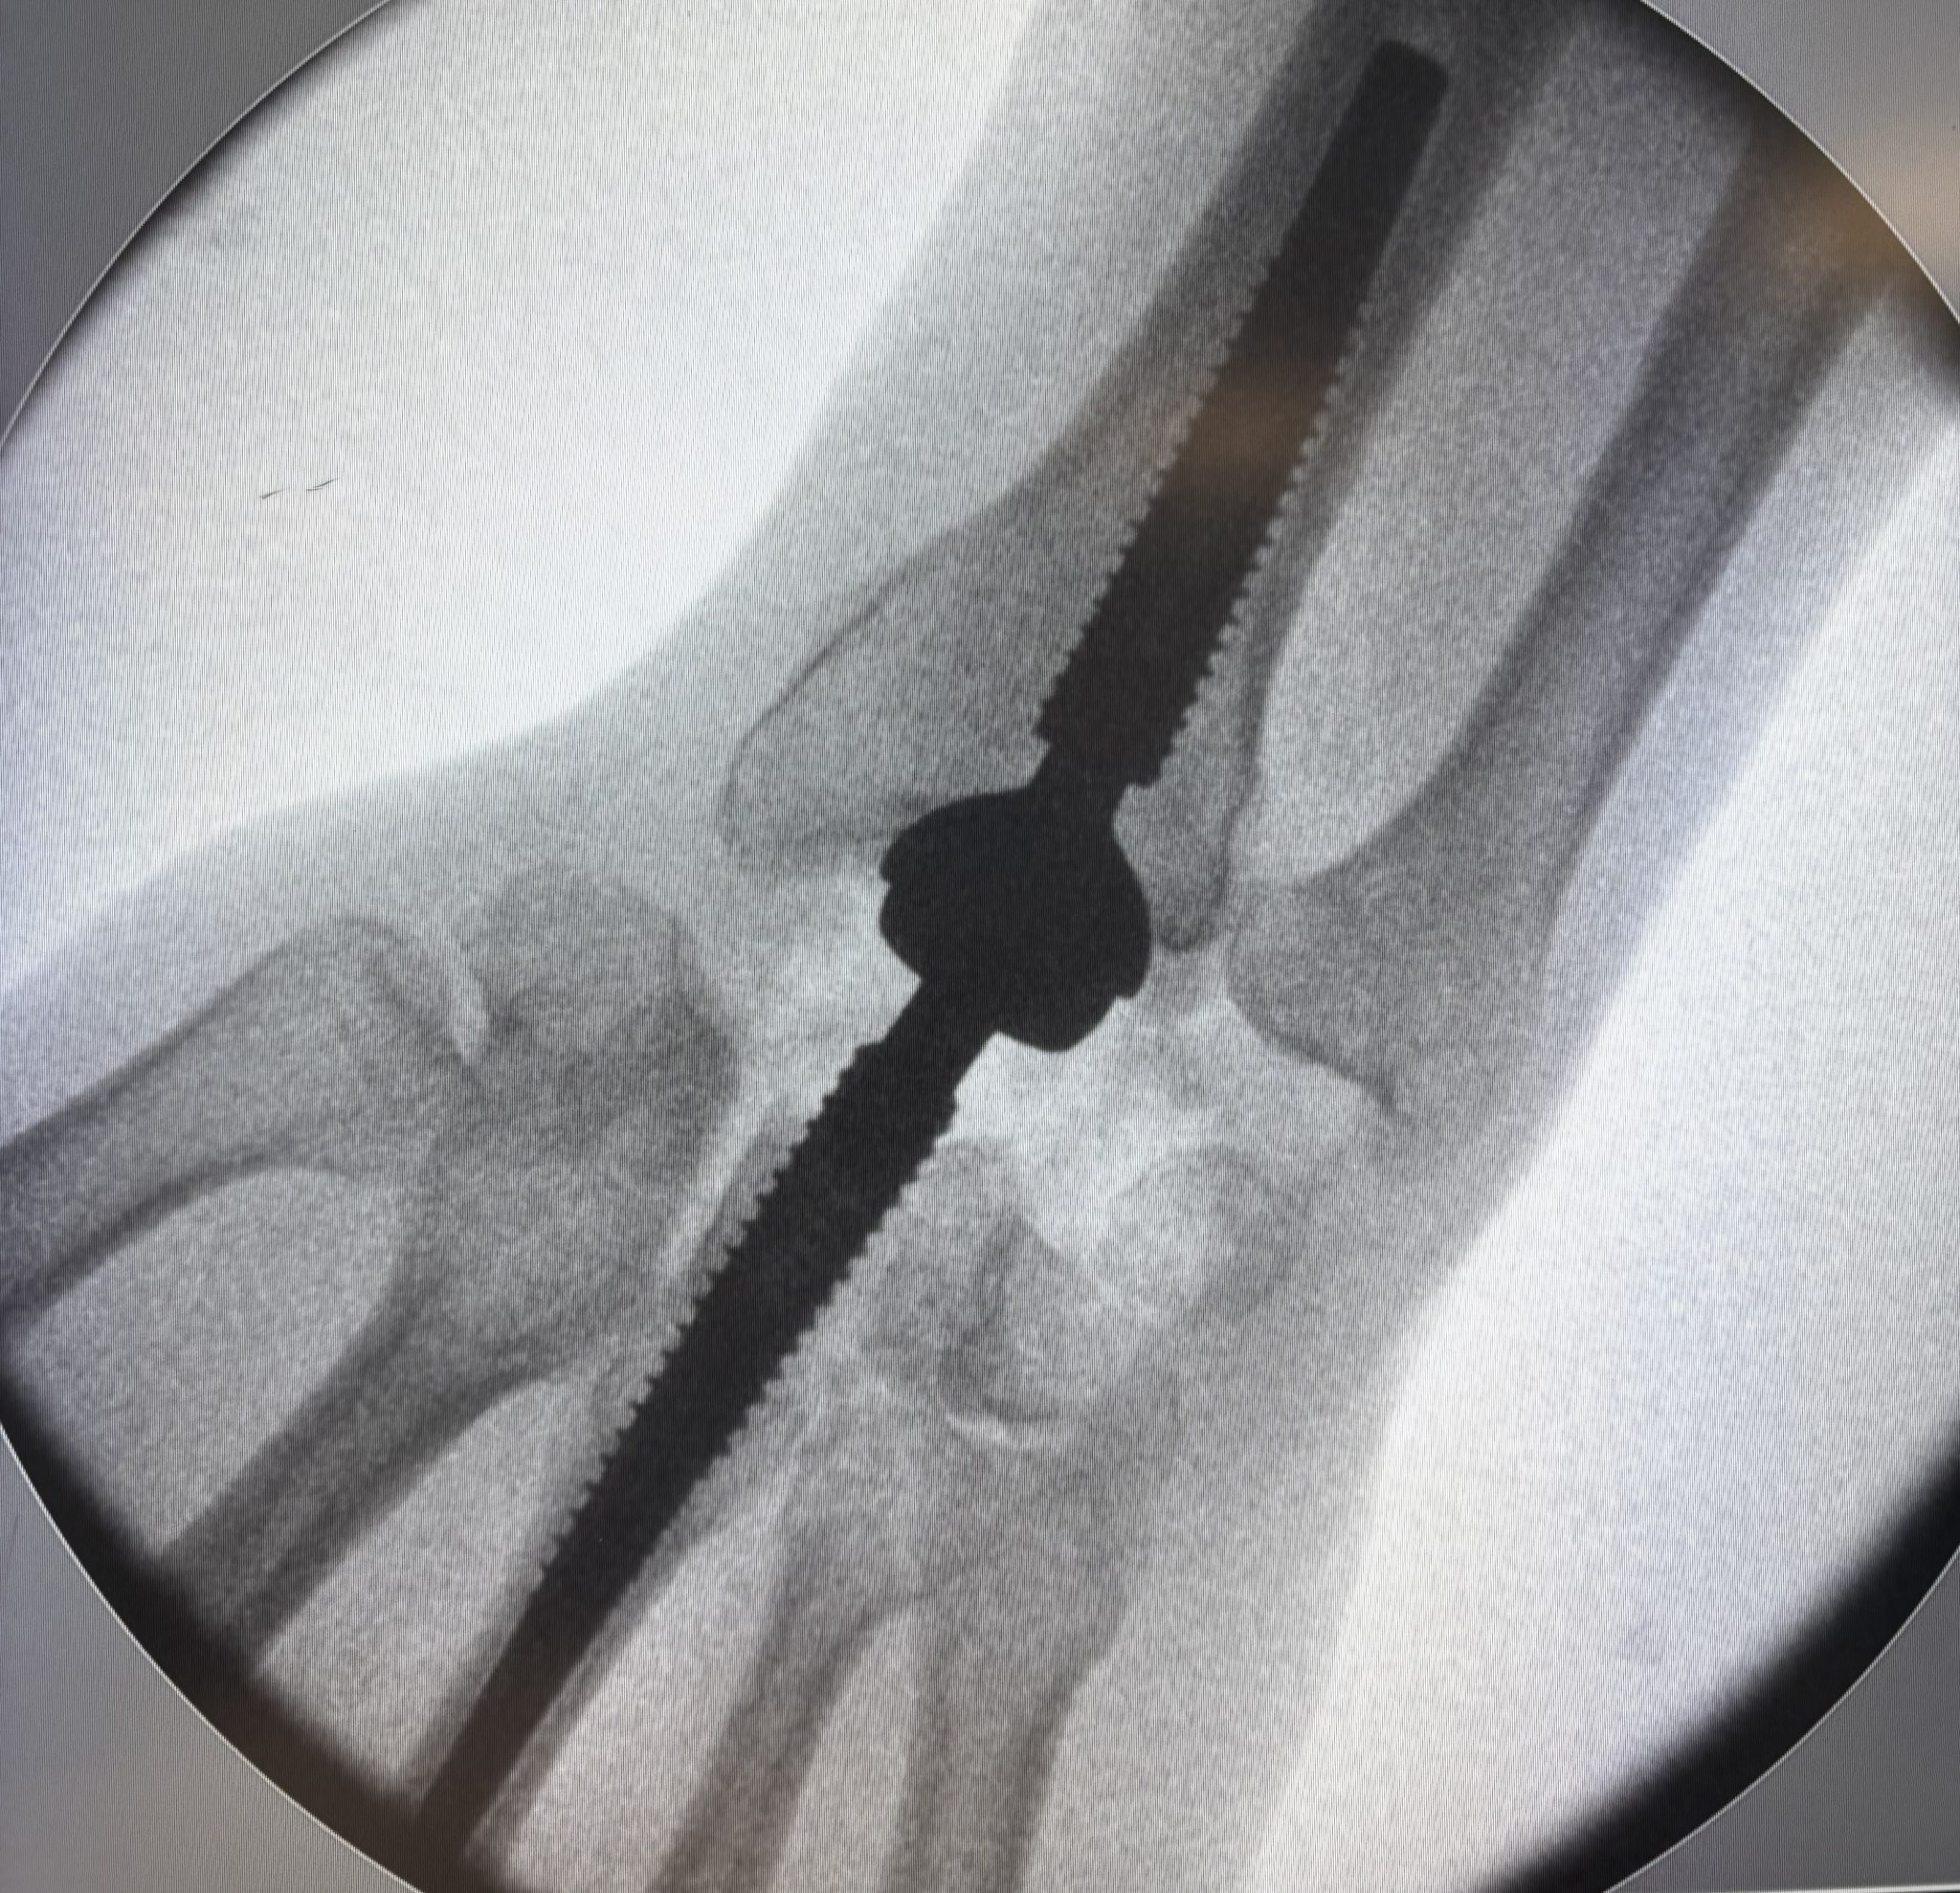

La prothèse totale de poignet est un implant médical destiné à remplacer une articulation du poignet sévèrement usée.

Elle est composée de plusieurs éléments artificiels permettant de restaurer une articulation fonctionnelle, tout en limitant la douleur.

Il existe aujourd’hui différents modèles de prothèses totales de poignet, utilisés en France.

Certains implants sont développés par des fabricants spécialisés comme Keri Médical, parmi d’autres dispositifs disponibles.

Le choix de la prothèse repose uniquement sur des critères médicaux :

Déroulement de la chirurgie du poignet

La chirurgie est réalisée au bloc opératoire, sous anesthésie locorégionale ou générale.